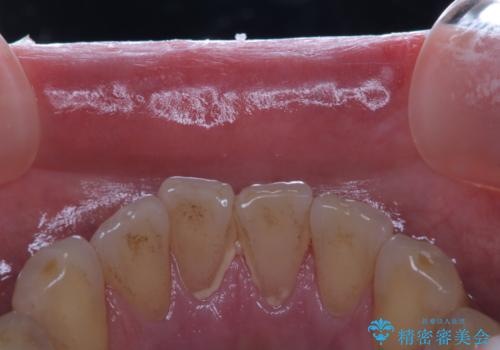

プラークが放置されると、そこで歯周病菌が繁殖し始めます。よって歯肉に炎症が生じ、歯周病に引き金となります。

クリーニングを行うことで、汚れがを取り除くだけではなく、口臭予防にもなります。